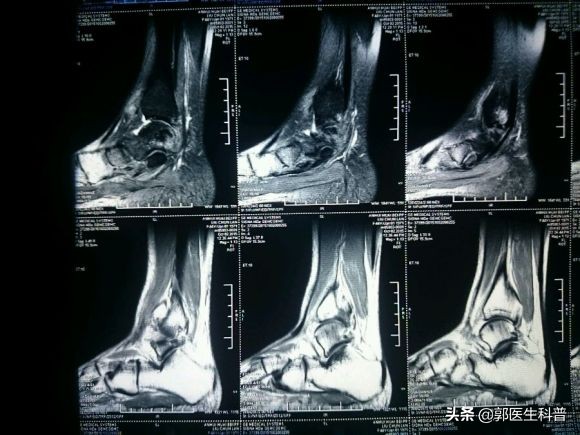

但是有一次在进行羽毛球运动时,他不小心扭伤了脚踝部,当时受伤的部位就肿胀疼痛的挺厉害,但是他认为自己身体健壮,休养几天就好了,所以一直没有重视,没有去医院检查,也没有规律治疗,后来受伤处消肿了,疼痛减轻了。但是仍感疼痛,每次走路多了或者运动就感觉脚踝部疼痛加重,他再也无法坚持继续他热爱的运动了,最后不得不去医院检查,核磁共振发现有韧带损伤,医生建议进行手术治疗,小勇花了很多钱,受了很多罪,也耽误了工作。所以,他很懊悔,为什么没有早一点去医院就诊治疗呢?

受伤后,首先看看受伤部位肿胀程度,以及疼痛程度,一般来说如果肿胀疼痛不是很重,可以自己尝试轻微活动脚踝部,但不要负重,脚踝疼痛不剧烈,大多是扭伤;但不要勉强走路,以免加重损伤,如果自己活动足踝时感觉剧烈疼痛,局部肿胀明显、皮下瘀血明显、不能站立和走动,疼的地方在骨头上,应立即去医院让医生面诊触摸检查,必要时行X线片、CT或者核磁共振检查,排除骨折韧带损伤,以免留下后遗症。